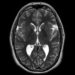

- Plaučių rentgenograma ar kompiuterinė tomografija – įvertinama, ar nėra pakitimų būdingų pneumonijai.

Tik atlikus tyrimus ir gavus atsakymus, galima patvirtinti legioneliozės diagnozę – ligai būdingi ne tik plaučių uždegimo, bet ir virškinimo trakto ar nervų sistemos simptomai.